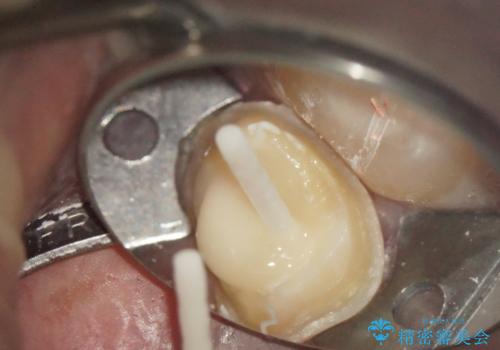

- 仮歯を製作し、根管治療をおこなう

→土台を築造後、かぶせ物を製作する

奥歯が感染をおこし強い痛みを出してしまっていたため、顕微鏡を用いた根管治療をおこない根管内を洗浄した後かぶせ物を製作しました。